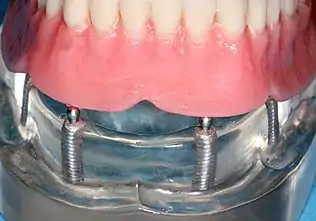

Four mandibular implants

Four lower implants to retain a complete denture with novaloc abutments

lower denture implant housing

Underside of a denture; housing fits like a ball and socket to hold the denture

Panorex radiograph showing implants

Xray of four Straumann implants and abutments

When a removable denture is worn, retainers to hold the denture in place can be either custom made or "off-the-shelf" (stock) abutments. When custom retainers are used, four or more implant fixtures are placed and an impression of the implants is taken and a dental lab creates a custom metal bar with attachments to hold the denture in place. Significant retention can be created with multiple attachments and the use of semi-precision attachments (such as a small diameter pin that pushes through the denture and into the bar) which allows for little or no movement in the denture, but it remains removable.[17]:33–34 However, the same four implants angled in such a way to distribute occlusal forces may be able to safely hold a fixed denture in place with comparable costs and number of procedures giving the denture wearer a fixed solution.[54]